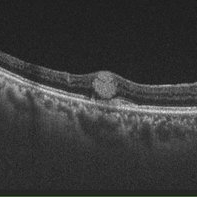

AZOOR

Sep 25 2025 by Hemanth Murthy, MBBS, MD, FASRS

OCT image of left eye of a 72 yr male with history of progressive loss of vision and loos of field of vision more in left eye. The OCT shows a trizonal pattern of outer retinal loss.

Photographer: Mr Veda Vyas

Condition/keywords: acute zonal occult outer retinopathy (AZOOR)